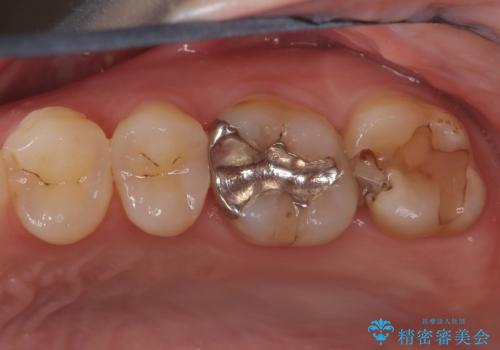

銀歯からセラミックへ。右上奥歯の精密根管治療と審美修復

担当医 河口智英